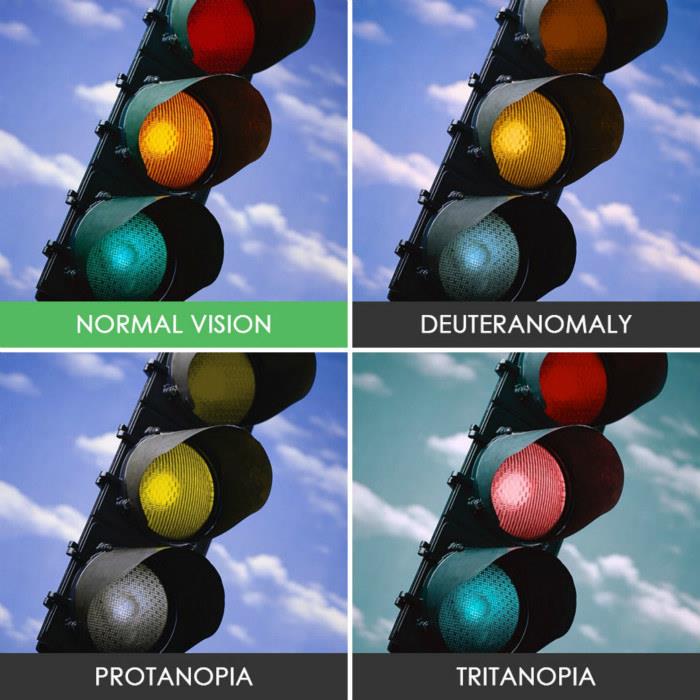

色盲只能看到黑白?

很多人认为色盲的世界是黑白灰的,其实这是对色盲最大的误解。

(正常 绿色盲 红色盲 蓝黄色盲)

(正常 绿色盲 红色盲 蓝黄色盲)

根据不同类型的色盲,以及色盲的严重程度,患者多少是能看到一些颜色的,或者说只是有些颜色看起来跟常人不同,但并不等于是“黑白”的世界。